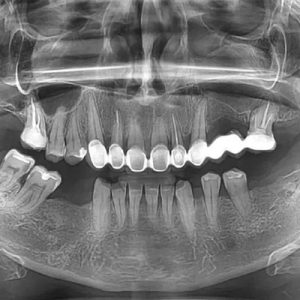

Digitalni

ortopan snimak

Ortopan panoramsko snimanje u ultra HD rezoluciji za 15 sekundi sa Low Dose senzorom.